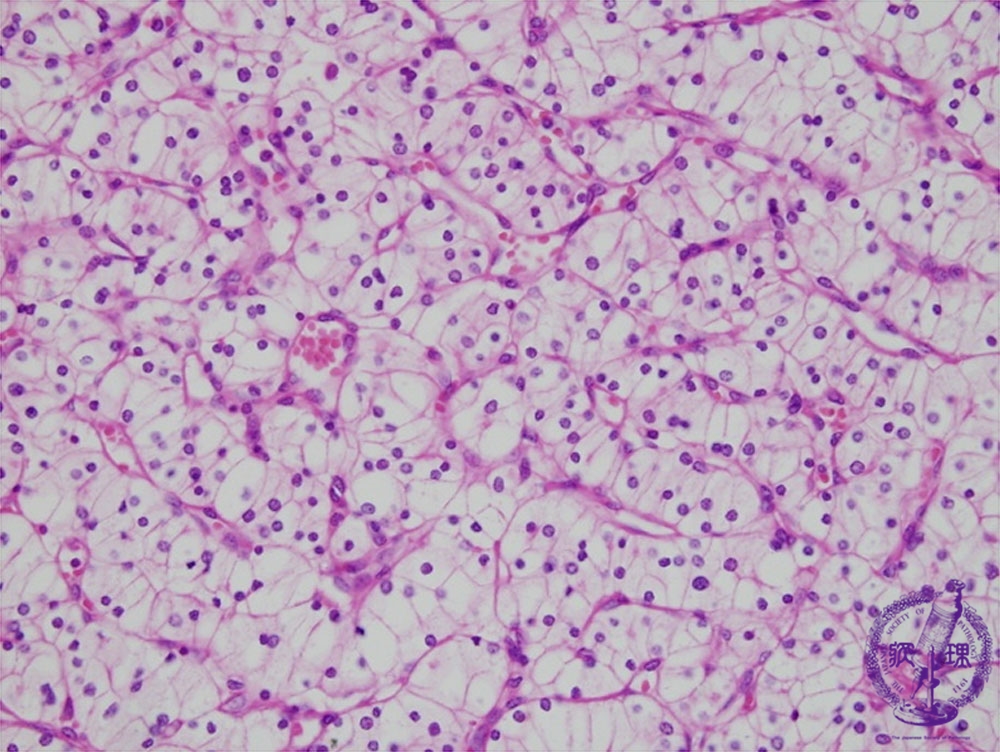

Microscopic findings (HE, high power view): Renal cell carcinoma (clear cell carcinoma). The tumor cells possess clear cytoplasm containing abundant glycogen and lipid.